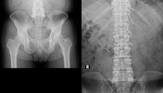

脊柱管狭窄症

73歳 男性 デスクワーク・PC操作

2年前 前立腺癌 ホルモン剤、抗がん剤にて経過観察中

検査所見(初検時)2019年 2月5日